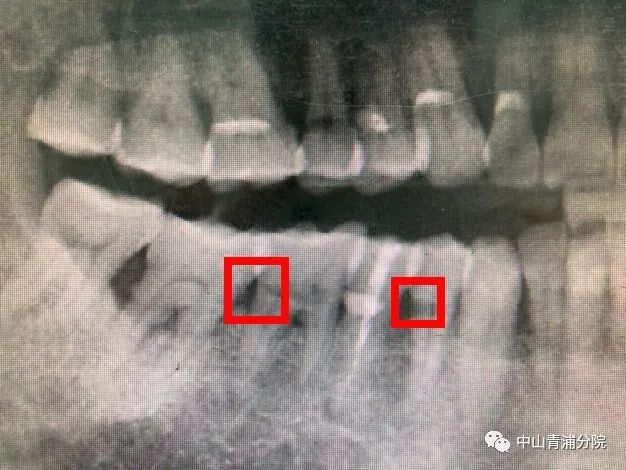

接诊医生进行检查后发现,刘老伯右侧下方第一颗前磨牙,第一颗磨牙颊侧可见深2mm缺损,探诊疼痛,冷测检查疼痛明显,持续近10秒,同时,X线片检查显示:颊侧缺损深至牙髓,伴随牙槽骨轻度吸收(图A)。医生为刘老伯制定了详细的治疗计划,随后为他进行了根管治疗(图B),为刘老伯后续的牙周治疗和修复治疗做准备。